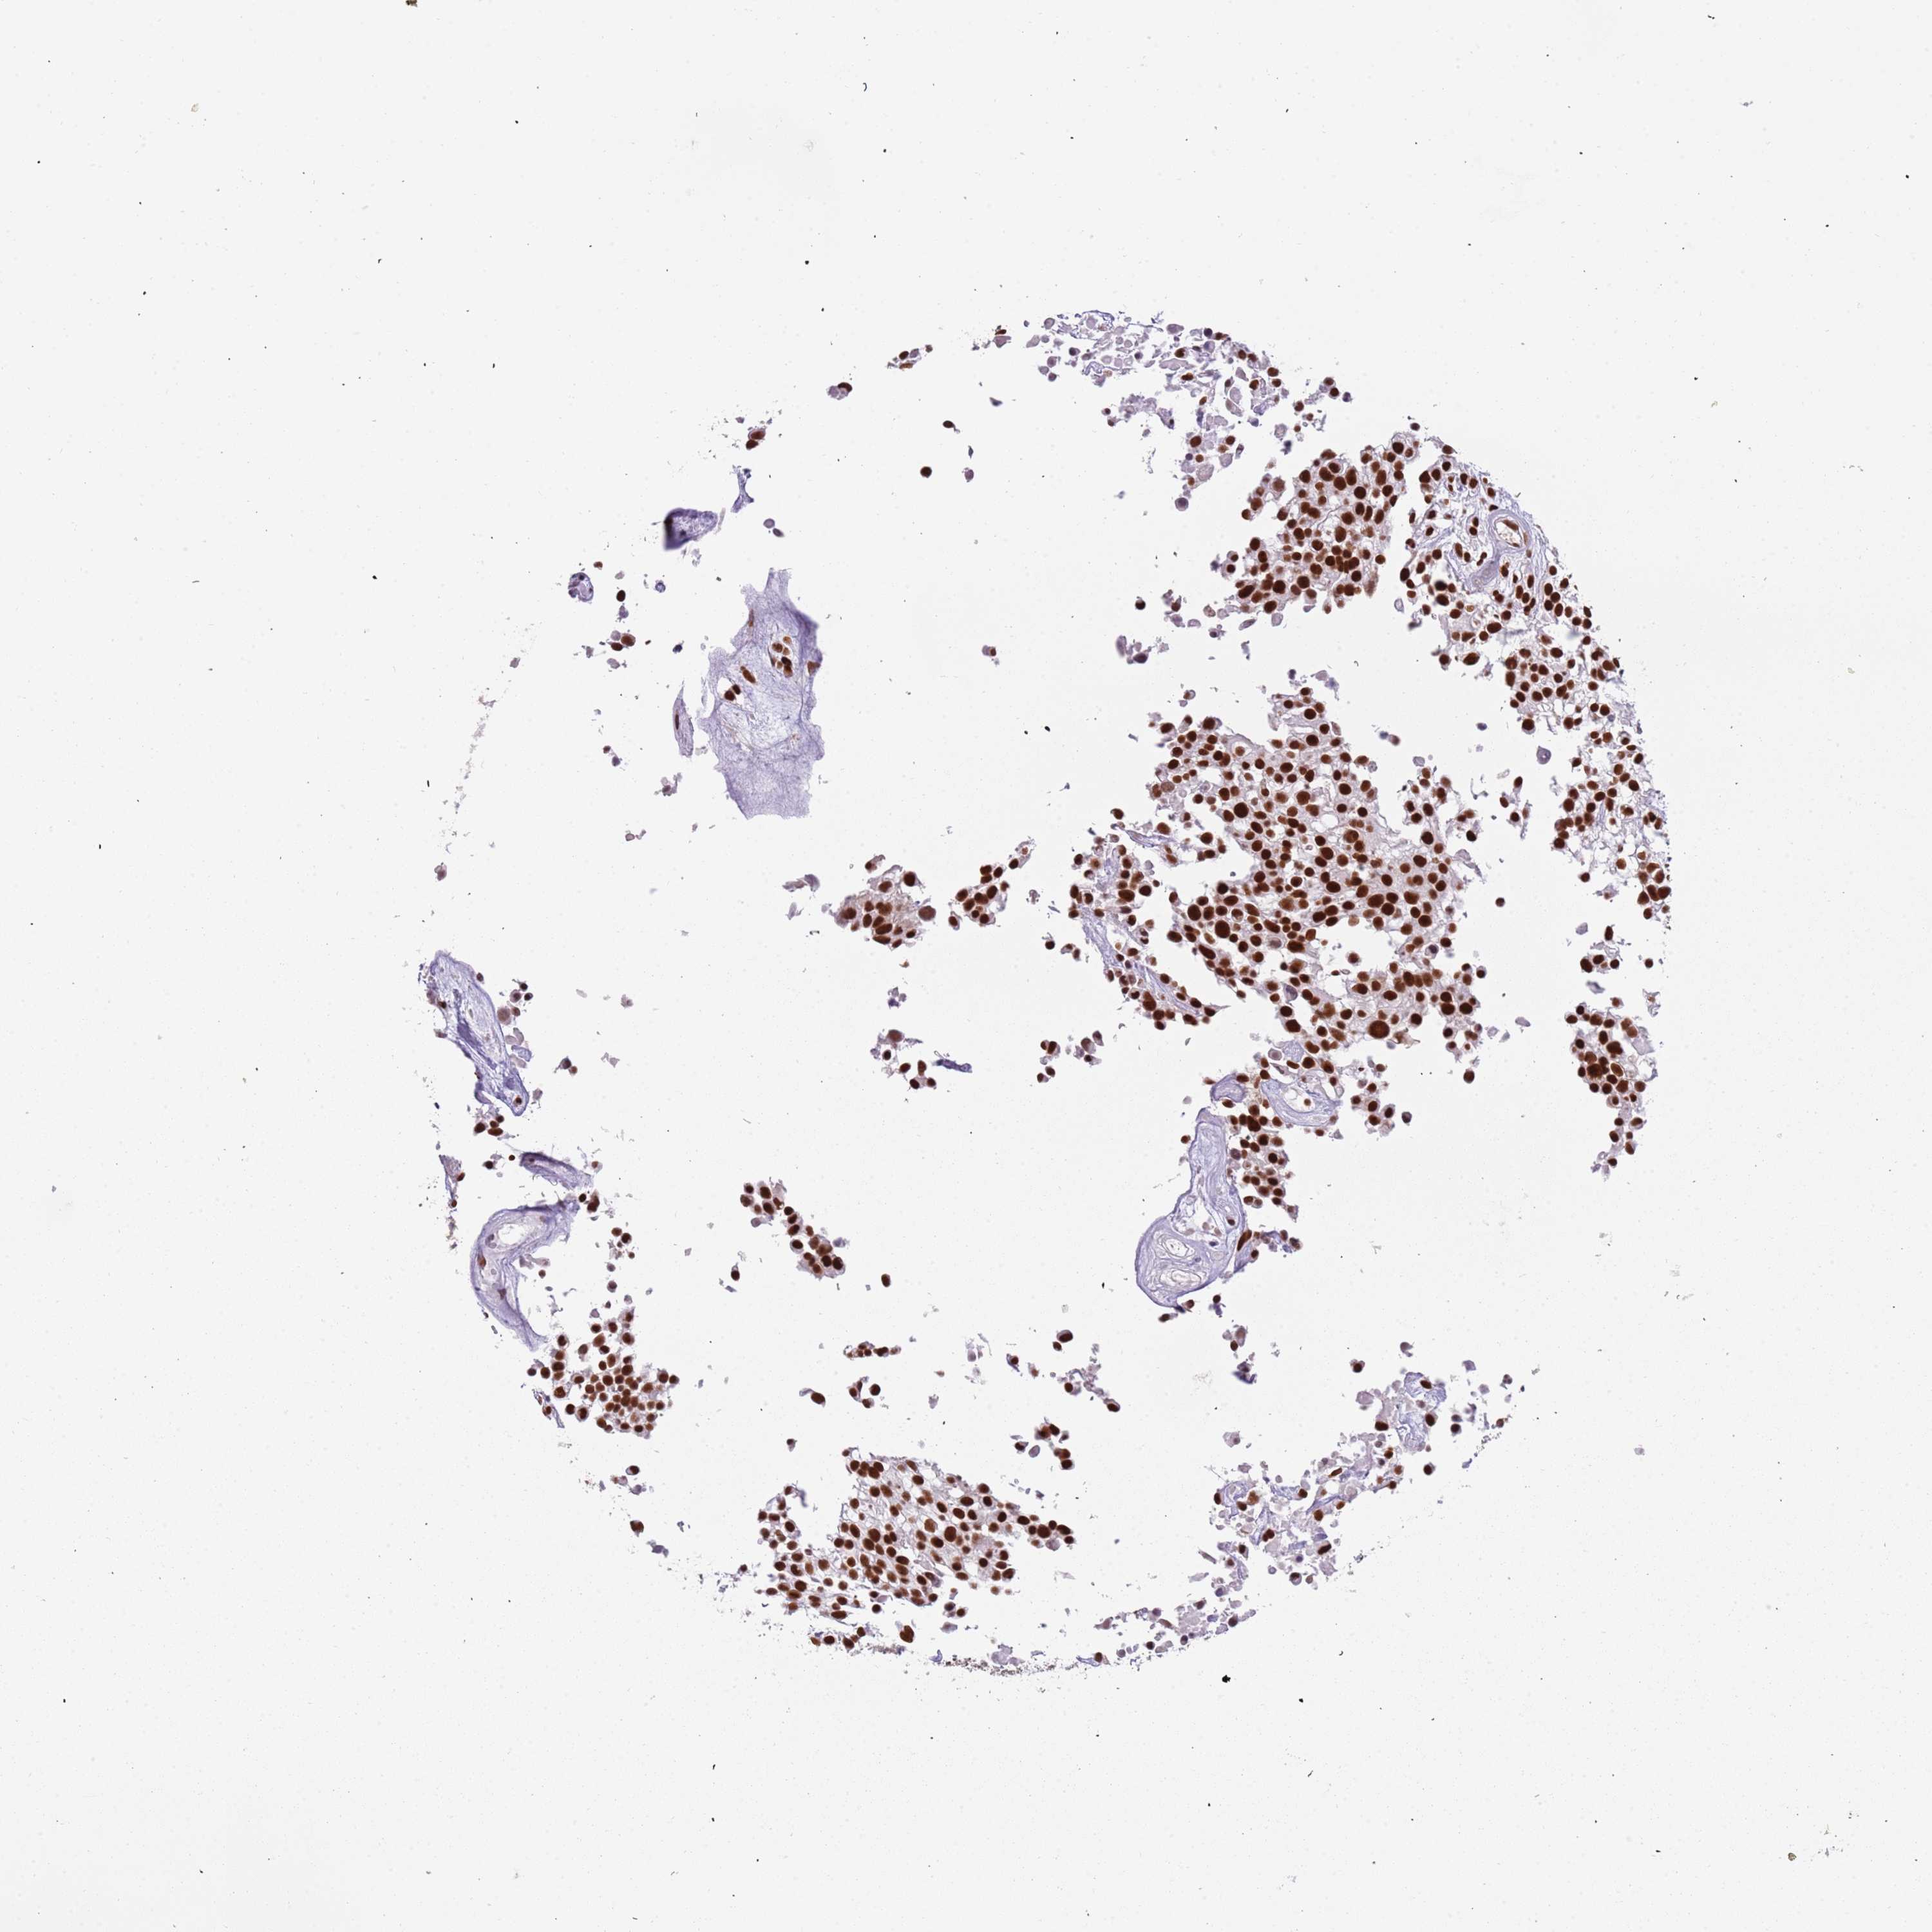

UROTHELIAL CANCER - Protein expressioni

A mouse-over function shows sample information and annotation data. Click on an image to view it in a full screen mode. Samples can be filtered based on level of antibody staining by selecting one or several of the following categories: high, medium, low and not detected. The assay and annotation is described here.

Note that samples used for immunohistochemistry by the Human Protein Atlas do not correspond to samples in the TCGA dataset.

Antibody stainingi

Antibody staining in the annotated cell types in the current human tissue is reported as not detected, low, medium, or high, based on conventional immunohistochemistry profiling in selected tissues. This score is based on the combination of the staining intensity and fraction of stained cells.

Each image is clickable and will lead to virtual microscopy that enables deeper exploration of all samples and also displays staining intensity scores, fraction scores and subcellular localization as well as patient and tissue information for each sample.

Antibody HPA042559

Antibody HPA044208

Staining

High

Medium

Low

Not detected

Intensity

Strong

Moderate

Weak

Negative

Quantity

>75%

75%-25%

<25%

None

Location

Nuclear

Cytoplasmic/membranous

Cytoplasmic/membranous,nuclear

Urothelial carcinoma, High grade